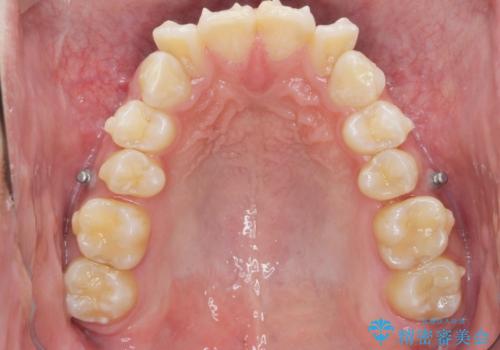

前歯のガタつきに加え、上顎が前にある咬合関係(上顎前突)を改善すべく、マイクロインプラントを用いた上顎奥歯の後方移動、拡大、ディスキングを用いたマウスピース矯正治療を計画します。

マイクロインプラントを使用したことで、しっかりと遠心移動が為され、良好な咬合関係が達成されました。